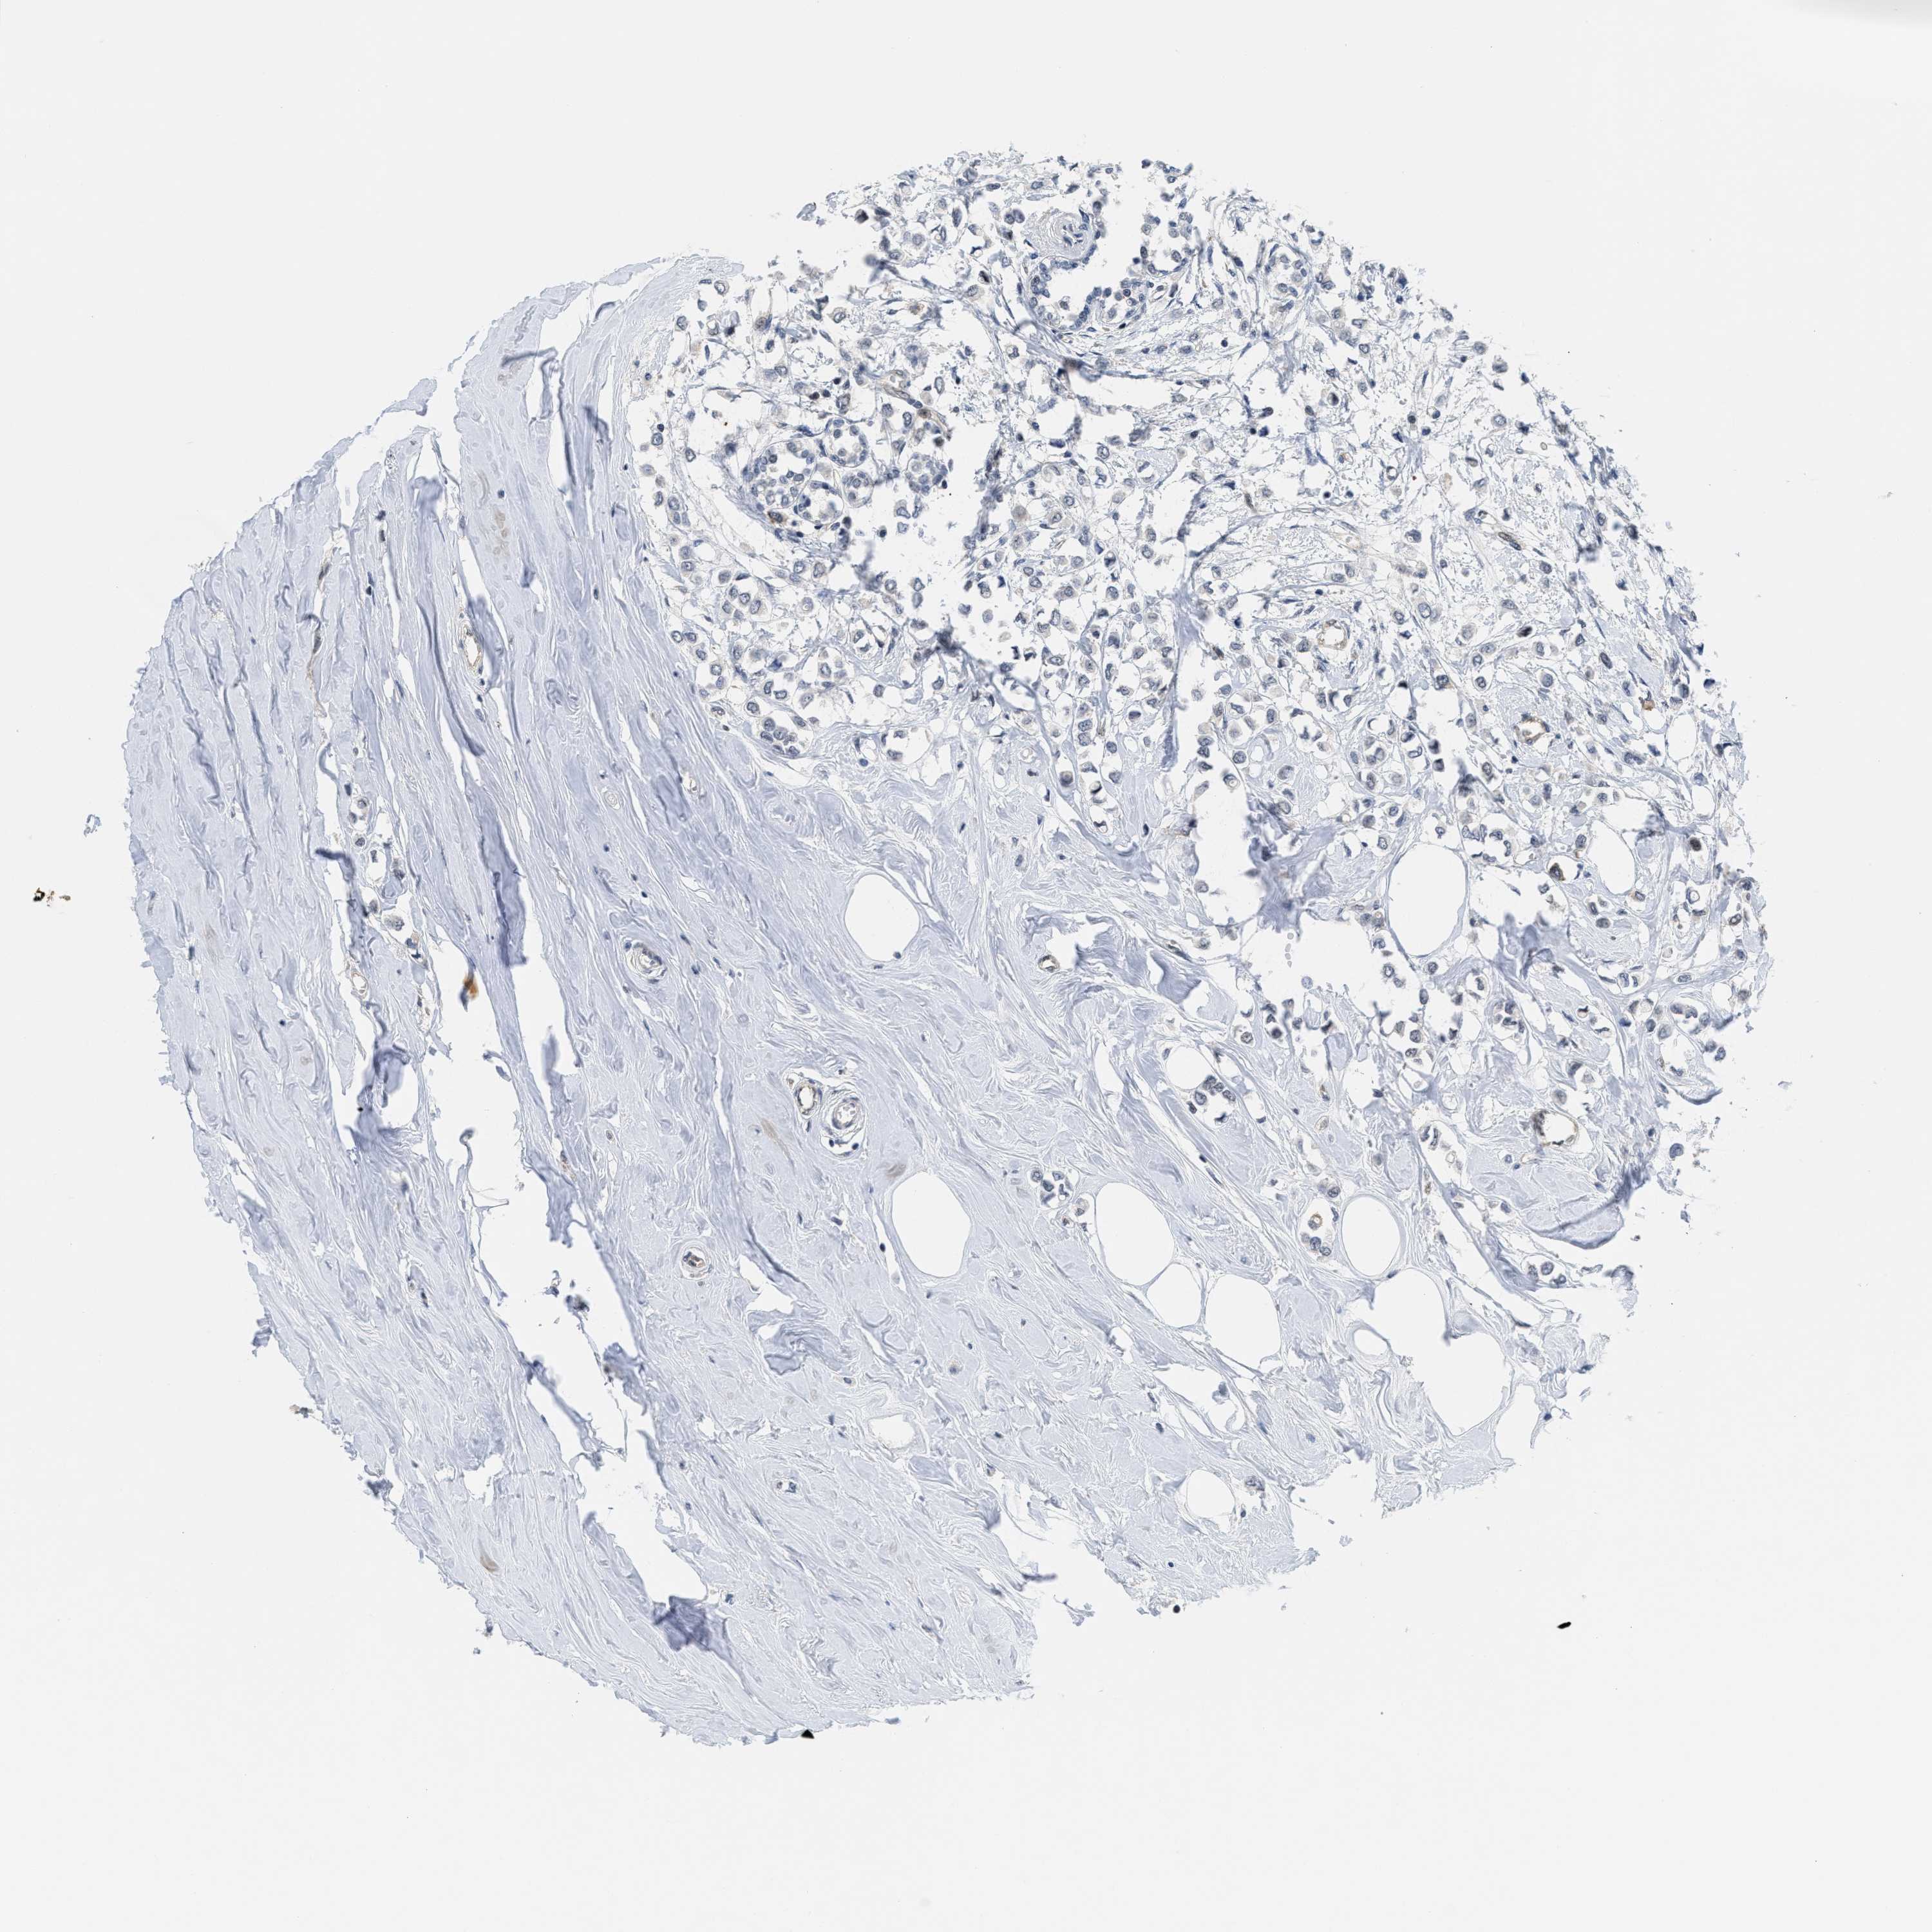

CANCER BREAST CANCER Show tissue menu

Breast cancer

Human cancer